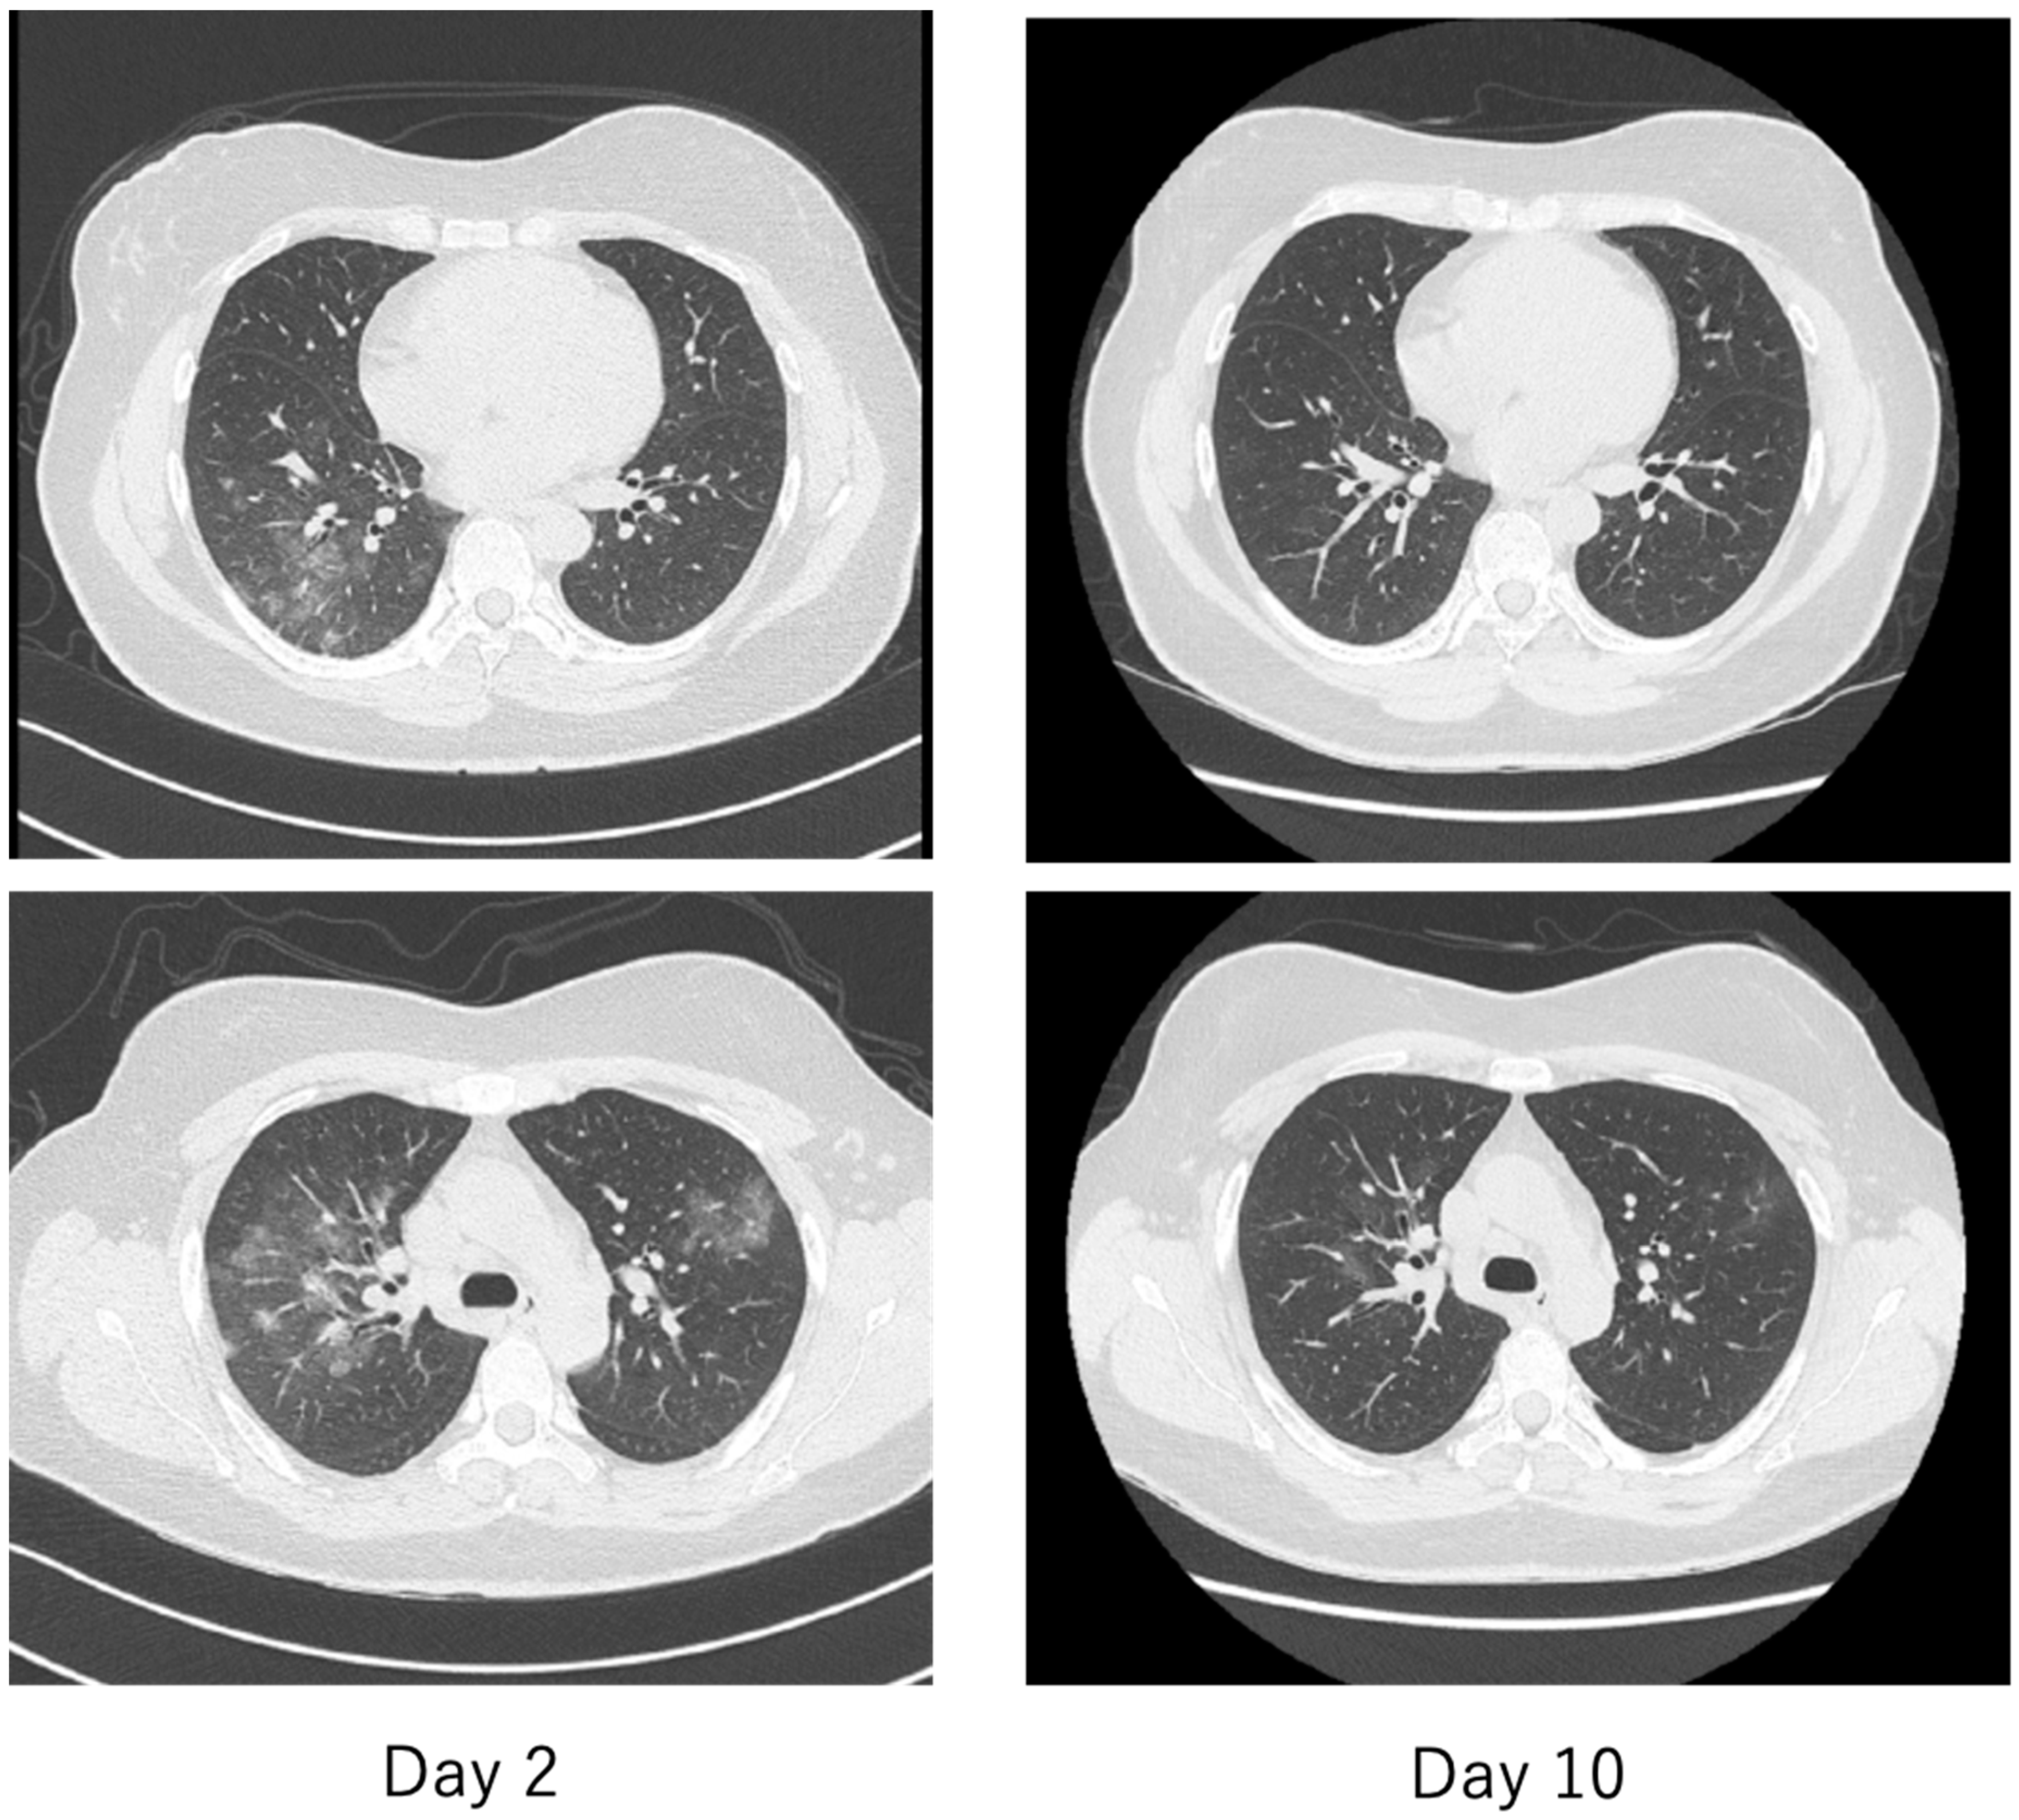

| Progressive multiple frosted shadows in both lungs | ||